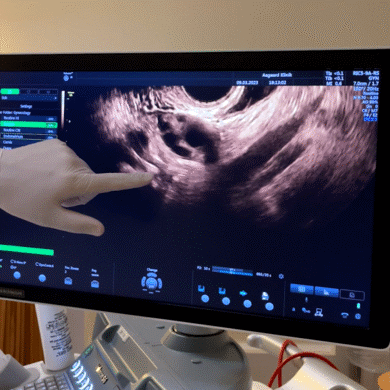

Camillas kamp i fertilitetsbehandling

Efter at have fået besked fra fertilitetslæge Aboubakar Cissé om, at det står rimelig skidt til med fertiliteten blandt danskerne, tænkte jeg, at det kunne være interessant at snakke med en kvinde, der netop kunne bidrage med det perspektiv. En kvinde, der har været igennem det, som mange af os kvinder frygter. Nemlig at få den nedslående besked om, at man har forringede chancer for at få sit ønskebarn og skal i fertilitetsbehandling.

Min søgen efter en kvinde, der kunne indvie mig i de tanker og følelser, der hører med en fertilitetsbehandling, førte mig til 27-årige Camilla Sparre. Hun har været i fertilitetsbehandling, siden hun var 23 år.

Hendes rejse har været fyldt med udfordringer og smerte, som hun beundringsværdigt har kæmpet sig igennem takket være hendes brændende ønske om at blive mor. Camillas inspirerende og rørende historie deler jeg i dette afsnit.